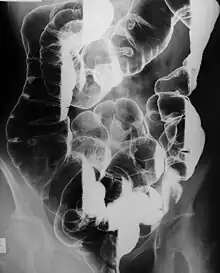

Barium enema radiograph showing multiple polyps (mostly pedunculated) and at least one large mass at the hepatic flexure coated with contrast in a patient with Peutz–Jeghers syndrome